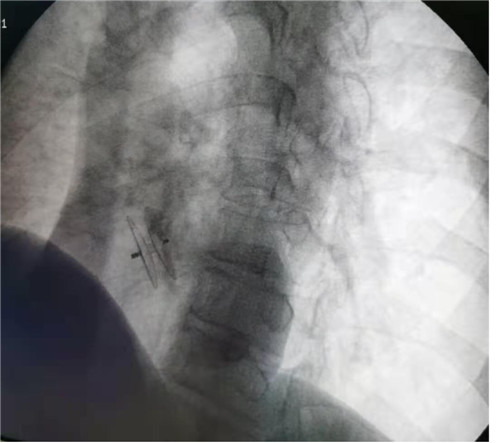

诊断明确,为快速解除患者症状,消除不适,经完善术前准备工作,2月26日,在姜永红主任带队下,胸心外科在DSA引导下经右股静脉途径将封堵器沿输送鞘置入并成功封堵卵圆孔,术中多角度显示封堵器形态良好。手术顺利,患者病情平稳,恢复良好,术后第2天痊愈出院。